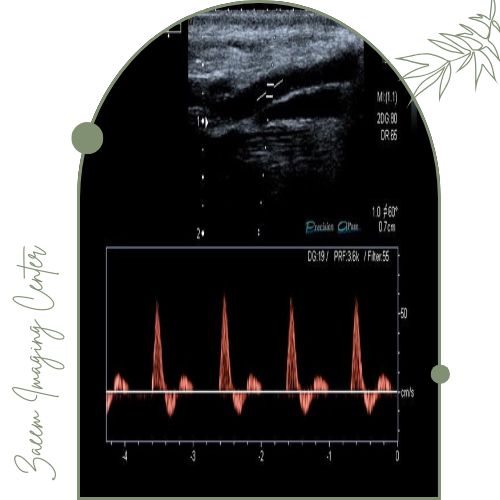

سونوگرافی داپلر یک روش تصویربرداری غیرتهاجمی و بسیار دقیق است که با کمک امواج صوتی با فرکانس بالا سرعت، جهت و الگوی جریان خون در رگهای سطحی و عمقی پا را بهصورت لحظهای بررسی میکند. در این روش متخصص میتواند عملکرد دریچههای وریدی وجود یا عدم وجود انسداد، شدت تنگی عروق، وجود لختههای خونی (DVT)، میزان برگشت خون (ریفلاکس وریدی) و حتی کوچکترین تغییرات در جریان خون شریانی و وریدی را تشخیص دهد.

این روش یکی از استاندارد ترین روش های تشخیصی در ارزیابی واریس، انسداد شریانی، اختلالات جریان خون در بیماران دیابتی و بررسی وضعیت عروق پس از درمانهای لیزر یا جراحی است.